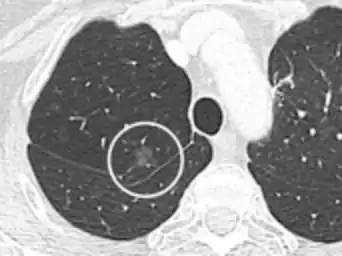

CT image in patient with COVID-19 showing bilateral ground-glass opacities at the periphery of both lungs.

Ground-glass opacity is among the most common imaging findings in patients with confirmed COVID-19.[16][17] One systematic review found that among patients with COVID-19 and abnormal lung findings on CT, greater than 80% had GGOs, with greater than 50% having mixed GGOs and consolidation.[16] GGOs with mixed consolidation has most often been found in elderly populations.[18] Several studies have described a pattern among initial, intermediate, and hospital discharge imaging findings in the disease course of COVID-19. Most commonly, initial CT imaging reveals bilateral GGOs at the periphery of the lungs. During initial stages, this is most often found in the lower lobes, although involvement of the upper lobes and right middle lobe has also been reported early in the disease course.[16][18] This is in contrast to the two similar coronaviruses, SARS and MERS, which more commonly involve only one lung on initial imaging.[19][20] As the COVID-19 infection progresses, GGOs typically become more diffuse and often progress to consolidation.[11][18] This is sometimes accompanied by the development of a crazy paving pattern and interlobular septal thickening.[18] In many cases the most severe pulmonary CT abnormalities occurred within 2 weeks after symptoms began.[17] At this point, many individuals begin showing resolution of consolidation and GGOs as symptoms improve. However, some patients have worsening symptoms and imaging findings, with further increase in septal thickening, GGOs, and consolidation. These patients may develop lung "white-out" with progression to acute respiratory distress syndrome (ARDS) requiring treatment escalation.[17][21]